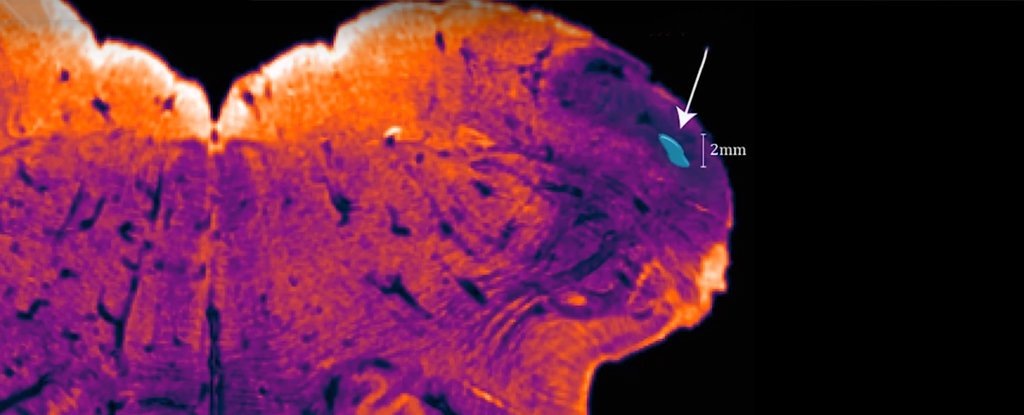

Само по себе веревчатое тело представляет пучок нервных волокон, по которому импульсы проходят от спинного мозга в мозжечок. Оно обрабатывает сенсорную информацию - по факту любую информацию, отвечающую за двигательную активность: поддержание позы, равновесия и осанки. Обнаруженное же учеными "ядро" расположено в нижней части веревчатого тела и, по мнению нейробиологов, играет ключевую роль в его функционировании.

Ядро веревчатого тела